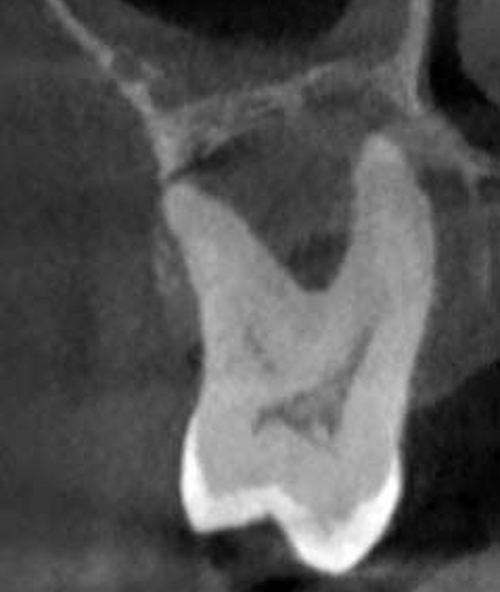

Tras un examen clínico y en algunos casos la realización de un Tac dental 3D o una Ortopantomografía, nuestro experto en periodoncia llevará a cabo una valoración y un plan de tratamiento personalizado para cada paciente.

1. DIAGNÓSTICO

Realizamos radiografías o un tac 3D y una serie de pruebas clínicas con una sonda periodontal para diagnosticar si existe enfermedad periodontal o no.

El curetaje dental o raspado, es un procedimiento odontológico en el que se raspa una bolsa de la encía inflamada y se elimina el sarro que se encuentra al interior. Luego se alisa la superficie de la raíz, esto parte de un tratamiento periodontal. Se requiere anestesia local para el procedimiento, por lo que el paciente generalmente no siente ningún dolor.